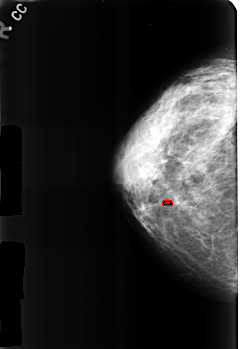

B_3184_1.RIGHT_CC

RIGHT_CC LINES 4536 PIXELS_PER_LINE 3120 BITS_PER_PIXEL 12 RESOLUTION 50 OVERLAY

FILE: B_3184_1.RIGHT_CC.OVERLAY

TOTAL_ABNORMALITIES 1

ABNORMALITY 1

LESION_TYPE CALCIFICATION TYPE LUCENT_CENTERED DISTRIBUTION N/A

ASSESSMENT 2

SUBTLETY 3

PATHOLOGY BENIGN

TOTAL_OUTLINES 1

BOUNDARY